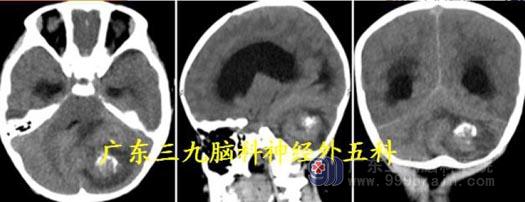

头颅MR:小脑蚓部、四脑室区示类囊状长T1 长T2 病灶,同时可见多发流空信号影,

并可见一粗大引流血管,病灶范围约40.8mm×40.8mm×52.7mm,增强后环壁不均匀强

化,边缘不光整。考虑血管母细胞瘤及幕上梗阻性脑积水。

MR 灌注测值395.61±232.75ml/100g/min;提示病灶高灌注,血供极其丰富。

CTA 及DSA:病灶主要由左侧小脑前下动脉、双侧小脑后下动脉参与供血;